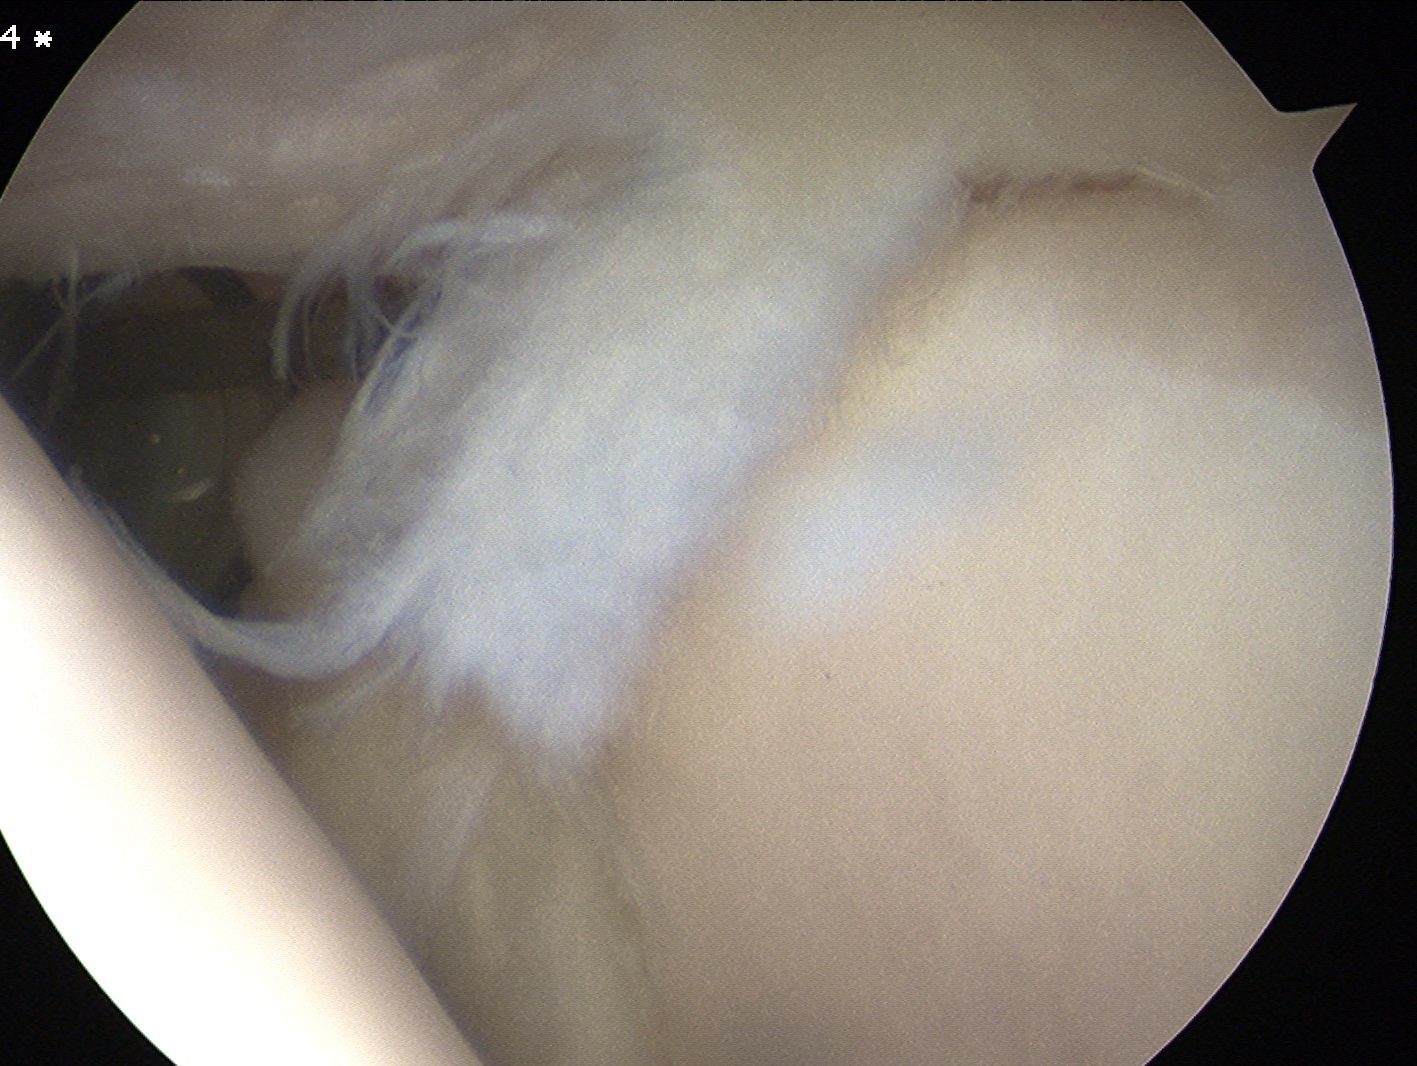

Snyder Arthroscopic Classification SLAP tears

| Type 1 (10%) | Type II (40%) | Type III (30%) | Type IV |

|---|---|---|---|

|

Superior labrum frayed Labrum and biceps anchor intact |

Superior labrum and biceps anchor torn off glenoid |

Bucket handle tear of superior labrum Biceps anchor intact |

Bucket handle tear of superior labrum and biceps tendon |